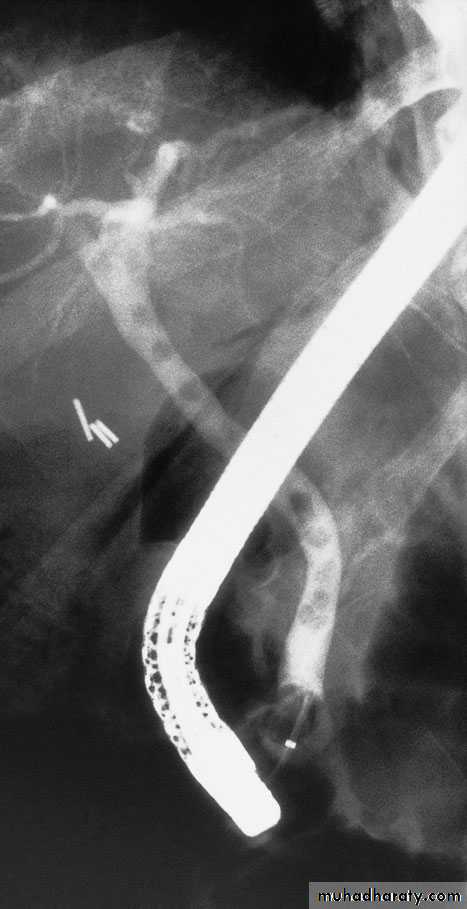

Endoscopic retrograde cholangiopancreatography: thepatient presented with jaundice 4 days after laparoscopic cholecystectomy.The bile duct contained multiple stones

Endoscopic papillotomy is the preferred first techniquewith a sphincterotomy, removal of the stones using a

Dormia basket or the placement of a stent if stone removal is not possible.

When the duct is clear of stones, a T-tube is inserted and the duct closed around it;

the long limb of the T-tube is brought out on the right side, and the bile is allowed to drain externally.

When the bile has become clear and the patient has recovered, a cholangiogram is performed, usually 7–10 days following operation.

If residual stones are found, the T-tube is left in place for 6 weeks so that the track is ‘mature’. The retained stones can be removed percutaneously by an interventional radiologist (Burhenne technique)